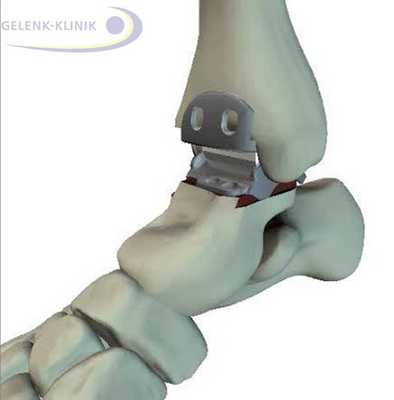

Артродез голеностопного сустава

Артродез (обездвиживание) голеностопного сустава при развитом артрозе — это золотой стандарт лечения в Германии. При нормальной скорости походка не изменяется. Нехватка подвижности компенсируется элементами кости предплюсны. Спортивная активность не запрещается. © Viewmedica

Обездвиживание кости в голеностопе после артроза может обеспечить безболезненность. Артродез верхнего голеностопного сустава помогает восстановить нагружаемость между таранной костью (Talus) и большеберцовой костью (Tibia) в повседневной жизни. Уже многие годы данная хирургическая методика является золотым стандартом в лечении артроза. Подвижность верхнего голеностопа устраняется при помощи терапевтического срастания костных структур. Таким образом, кости стопы срастаются так же, как и после переломов.

После терапевтического укрепления пациент сможет оказывать прежние нагрузки на стопу, держа её в нормальном положении. Во время ходьбы с нормальной скоростью вращательная способность почти не нарушена. Лишь при быстрой ходьбе либо беге, что требует повышенной подвижности лодыжки, наблюдается изменение походки. При нормальной ходьбе утраченная подвижность компенсируется суставами предплюсны.

Артродез голеностопного сустава имеет большое значение в лечение артроза. Болезненные ощущения в верхней части голеностопа, часто связанные с деформациями и повреждениями, хирурги Геленк Клиники устраняют при помощи данного хирургического вмешательства. Даже в эпоху эндопротезирования суставов, артродез всё ещё остается наиболее эффективным оперативным методом лечения. Все другие методики лечения должны оцениваться на основании результатов операции по обездвиживанию.

Артродез голеностопного сустава редко приводит к жалобам. Результаты более чем удовлетворительны, независимо от возраста пациента. Операция в Геленк Клинике в Германии обеспечит Вам более 25 лет безболезненной жизни. Кроме того, артродез поможет пациентам с сильным разрушением голеностопа, а также людям, страдающим лишним весом, добиться улучшения качества жизни.

Артродез помогает восстановить безболезненность и потерянную подвижность. Данное вмешательство требует использования специальных винтов и интрамедуллярных гвоздей. Они фиксируют сустав до полной оссификации. © Gelenk-Klinik

Артродез голеностопного сустава проводится и при использовании интрамедуллярных гвоздей, которые соединяют большеберцовую кость с таранной и пяточной. Артроз нижнего голеностопа и тяжелые травмы пяточной кости требуют проведения данной методики. Применение интрамедуллярных гвоздей для обездвиживания голеностопа приводит ещё и обездвиживанию сустава между пяточной и таранной костью. © Gelenk-Klinik